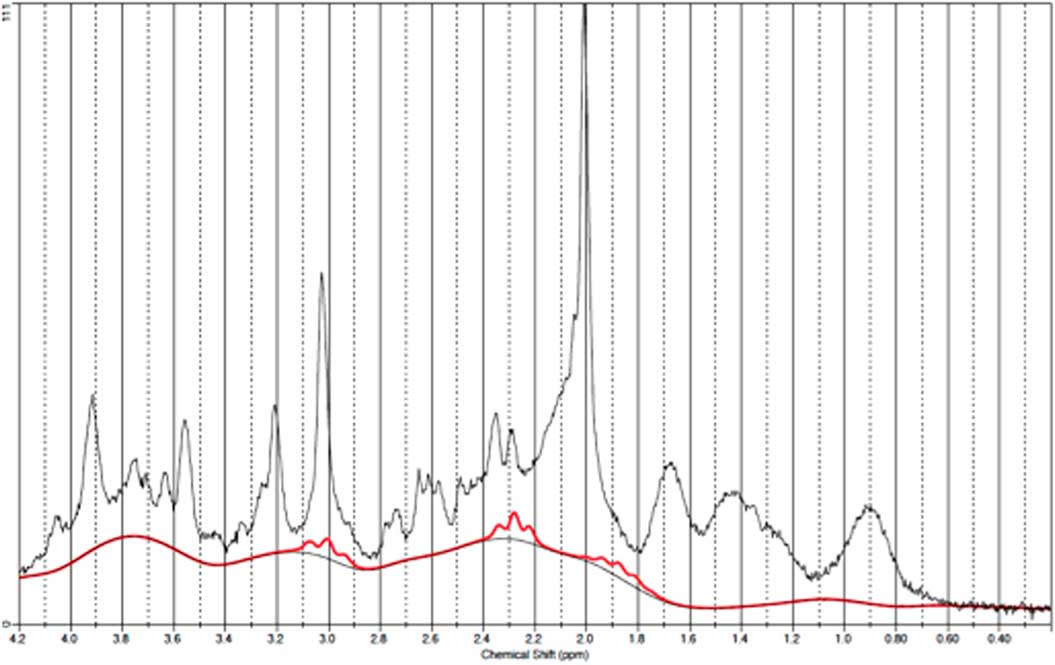

GABA measurements in OCC

Data from one occipital follow-up scan was discarded due to poor spectral quality. Figure 6 illustrates a representative spectra from OCC and Fig. 7 an individual plot for the GABA signal in OCC. When performing direct comparison between patients at baseline and healthy subjects, we found no significant difference in GABA/Cr ratios t(21)=0.37, p=0.72. The same applied when comparing pre- and post-ECT GABA/Cr levels in patients t (20)=0.78, p=0.47. Moreover, no significant correlation was found between pre-ECT GABA/Cr levels and HAM-D17 ratings (p=0404).

Fig. 6 Example of a representative spectrum from the occipital cortex. The raw data are plotted as a thin black curve. The thick red curve is the LcModel fit to this data. The baseline is also plotted as a thin black curve. At the top are plotted the residuals.

Fig. 7 Example of an individual plot for γ-aminobutyric acid from the occipital cortex. The raw data are plotted as a thin black curve. The thick red curve is the LcModel fit to this data.